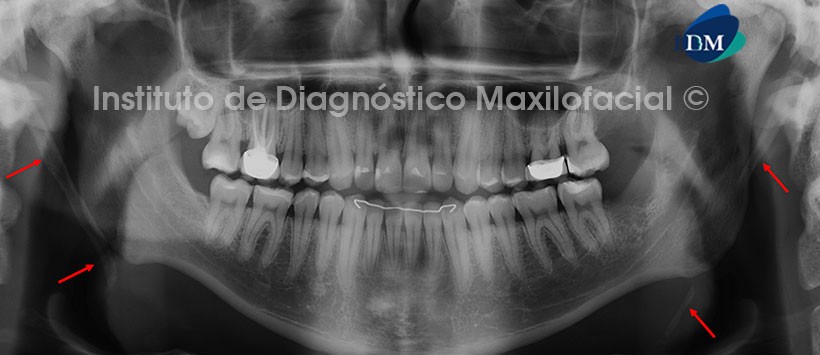

A la evaluación de la radiografía panorámica se aprecia material de obturación de conducto parcial en pieza 1.1 con probable proceso a nivel apical. Así mismo presenta material de obturación de conducto en piezas 1.6 y 4.6, restauraciones coronales múltiples. (Figura 1)

A la evaluación de la tomografía volumétrica (CBCT) en cortes axiales (Figura 2), transaxiales (Figura 3) y tangenciales (Figura 4), se evidencia proceso osteolítico que compromete la zona apical de la pieza 1.1, de forma redondeada, corticalizada de aproximadamente 9.60 mm de diámetro y 0,42 cc de volumen. A nivel intracanal apreciamos material de obturación de conductos parcial no se evidencia obturación en el conducto en el tercio apical, el mismo que se aprecia parcialmente obliterado. Incidentalmente se observa lesión apical en la pieza 2.1.